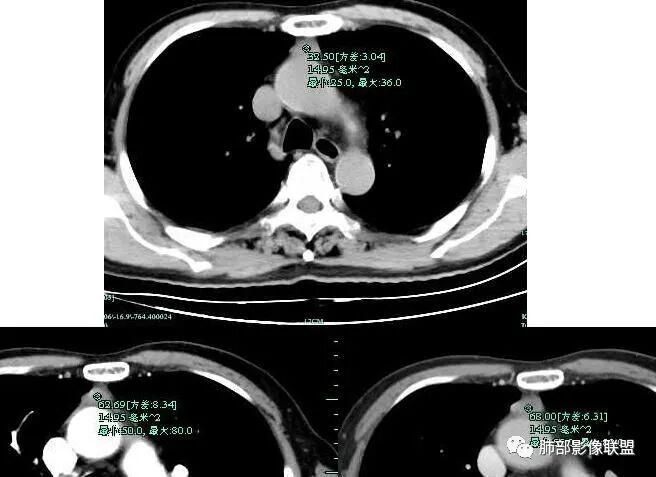

秦化君:前纵隔结节影,边缘清晰光整,质软,密度较均匀。增强较明显强化。考虑前纵隔良性病变,胸腺瘤?纵隔窗第一层面病灶内似有低密度,畸胎瘤待除外。

宇宙:前纵隔正中软组织结节,边缘光整, 与血管脂肪间隙欠清,中度强化,似有条状低密度影,考虑低危胸腺瘤,鉴别胸腺囊肿,胸腺增生结节。巴伟:前纵隔胸腺区结节,边缘平直,测量有强化,伪影?先考虑胸腺囊肿,淋巴结?胸腺瘤待排。

前纵隔结节灶,胸膜侧边缘平直内收,明显强化,但要除外容积效应,最好不同气相观察,除外囊肿。周太狼:前上纵隔占位,边缘光滑,软,密度均匀,中度强化,纵隔内余部位及双肺无明显异常。首先考虑胸腺瘤或胸腺增生,鉴别节细胞神经瘤。小兜:老年男性,体检发现前纵隔占位,边缘光整,密度较均匀,增强均匀轻度强化,右侧内乳血管增粗,考虑为良性病变,胸腺瘤可能。

闫美利:前纵隔结节,密度均匀,边缘光滑,类三角形,张力不高,强化明显,从强化角度考虑胸腺瘤,从概率考虑囊肿(黄勇老师说过小的病灶囊肿发生要远远大于瘤),部分层面感觉病灶软软的趴在主动脉上,综合考虑胸腺囊肿。

流心明智:老年男性,前纵隔正中结节影,边缘光整, 密度较均匀,纤维分隔?未见纵隔淋巴结大,强化较明显,似有条状低密度影。考虑:胸腺瘤,鉴别胸腺囊肿等。一切∮随缘:前纵隔类圆形结节,形态规则,边缘清晰,平扫密度均匀,增强后不均匀渐进性强化,老年男性,体检发现,考虑胸腺瘤。

傅昌瑜:老年男性,体检发现前纵隔占位。病灶边缘光整,无分叶,与周围血管间有脂肪间隙,内密度较均匀,强化明显。老年人,排除生殖细胞瘤,无脂肪密度,排除畸胎瘤。病灶膨胀感不明显,没有到处钻,考虑良性病变,强化明显,巨淋?注意鉴别胸腺瘤。王秀仙:前纵隔结节,边缘光滑清晰,近似三角形,紧贴主动脉弓,与主动脉弓间脂肪间隙部分消失,强化明显,考虑胸腺瘤。常规这么小的病灶,三角形的,感觉软软的,首先应该考虑胸腺囊肿,但是强化不符合。秋实:前纵隔类似软组织密度结节,略扁趴在主动脉前方,感觉比较软,边缘光滑,密度均,增强可见中度强化,有强化考虑胸腺瘤,形态考虑囊肿。

Lenle董:前纵隔结节,边缘光整,密度较均匀,较软,中度强化,考虑良性病变,胸腺瘤可能。水晶石头:患者老年男性,体检发现纵隔占位1周。胸部CT:前纵隔实性结节,边缘光整,无分叶,与周围血管间有脂肪间隙,内密度较均匀,强化明显。病变位于胸腺,考虑胸腺瘤,鉴别胸腺囊肿。浪迹天涯:前纵隔,边缘光滑,病灶上方见多个小结节堆积,同侧内乳静脉增粗,所以把淋巴瘤放在前面,胸腺瘤待排。

“纵隔”鳞状细胞癌(C型胸腺瘤,大小3×2×1.2cm)。免疫组化:CK(+++)、EMA(++)、Ki-67约65%(+)、TdT(-)、P63(+++)、P40(+++)、CD117(++)、CD5(+)、Syn(-)、CD99(+)。